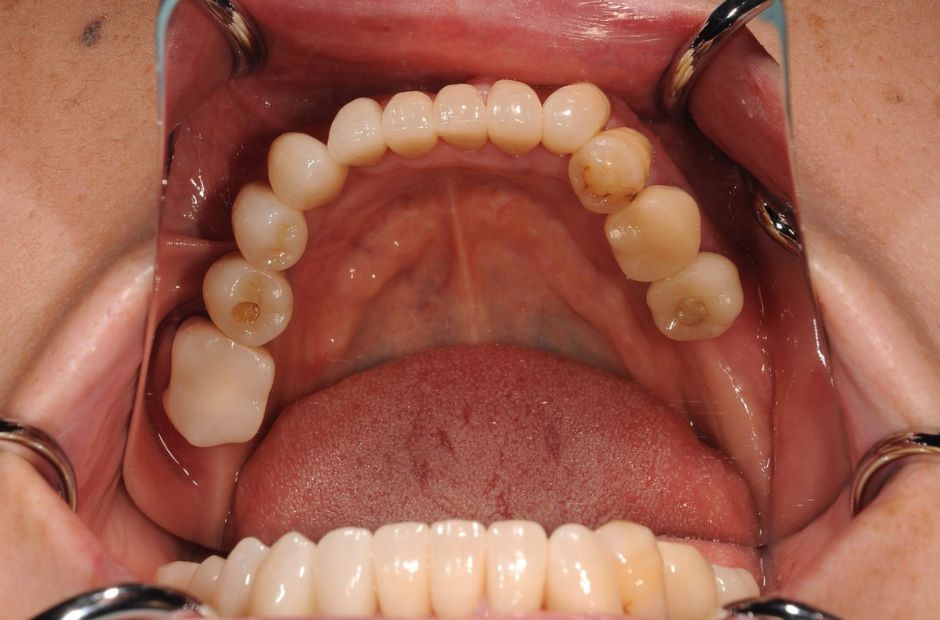

Case

当院のインプラント治療例

インプラント治療は、自然な歯を維持することが不可能な場合に、患者様の口腔機能と美観を回復するための重要な手段のひとつです。私たちは、患者様の状況に合わせた治療計画を提供し、自然な歯の代替としてのインプラントの役割を明確にします。症例の治療期間・回数は、症状や状態によって変わる場合があります。